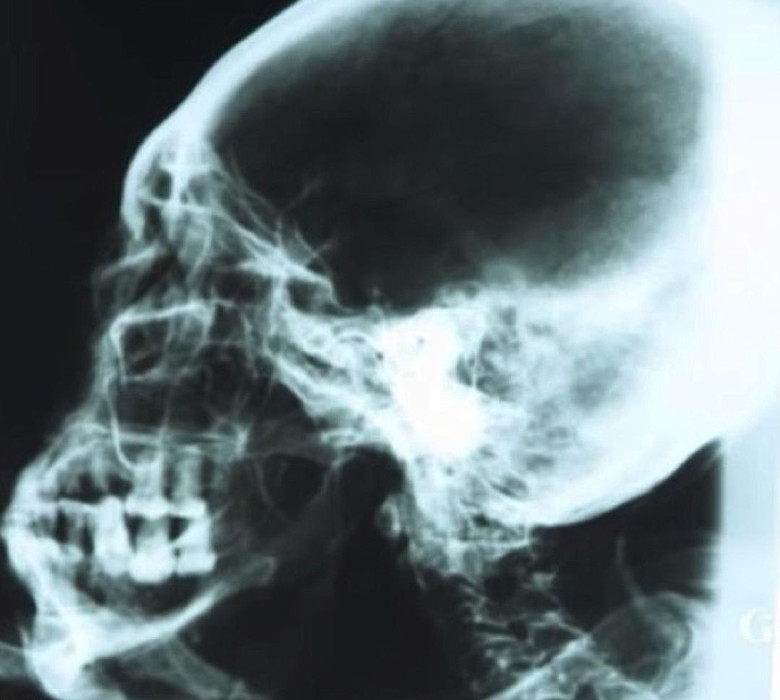

A múmiát valamilyen porral meghintjük (Korotkov professzor meghatározta hogy balzsamozó anyag), tehát első pillantásra úgy tűnik gipszszobor, bár röntgen, mint a számítógép tomográfia, megmutattam – belül van egy normál csontváz, és szintén a belső szervek maradványai. A szénhidrogén elemzés szerint a múmia korát meghatározzák – 2300-2500 év.

Mint N. Zaloznaya mondta, ennek a múmiának a testaránya általában tisztán embernél a humanoid növekedése 168 centiméter. de itt a fej és a végtagok természetesen meglepőek. A koponya hosszúkás, hosszúkás hát, az orr kicsi, gyakorlatilag nincsenek fülek, helyettük – kis lyukak a koponyban.